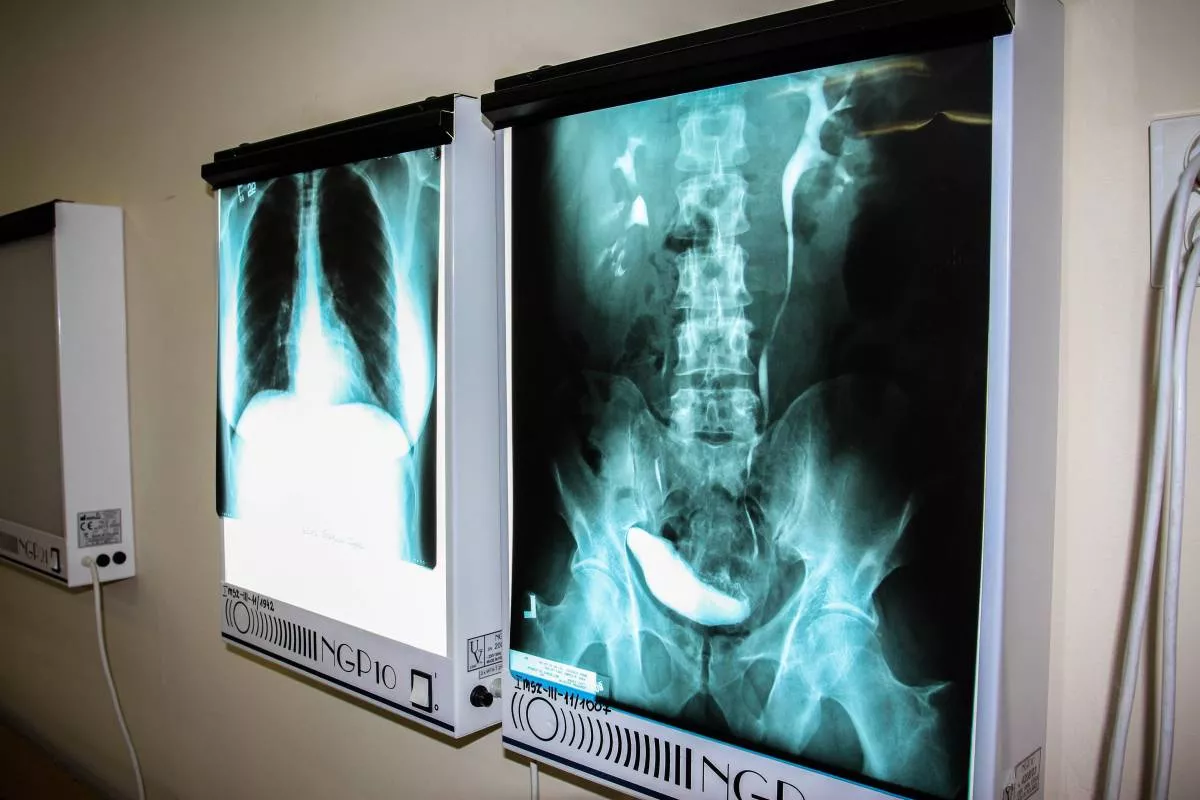

Technik elektroradiolog świadczy usługi medyczne w zakresie elektroradiologii w zakładach i pracowniach diagnostyki obrazowej, elektromedycznej, medycyny nuklearnej i radioterapii. Jego głównym zadaniem zawodowym jest wykonywanie zleconych przez lekarza badań i terapii oraz przygotowanie ich wyników do oceny. Do realizacji ww. zadania wykorzystuje: promieniowanie jonizujące, izotopy promieniotwórcze, zjawisko rezonansu magnetycznego, prąd elektryczny, ultradźwięki.

- wykonywać określone badania i zabiegi z diagnostyki obrazowej (m. in. zdjęcia RTG, badania mammograficzne, badania TK i MNR),

- Diagnostyka obrazowaPoznasz różne metody diagnostyki człowieka.

- RadiodiagnostykaPoznasz różne schorzenia rozpoznawane przy pomocy promieniowania rentgenowskiego oraz pola magnetycznego.

- Diagnostyka obrazowa - ćwiczeniaPoznasz sposoby układania pacjenta i wykonywania badań np. RTG, TK, MR.